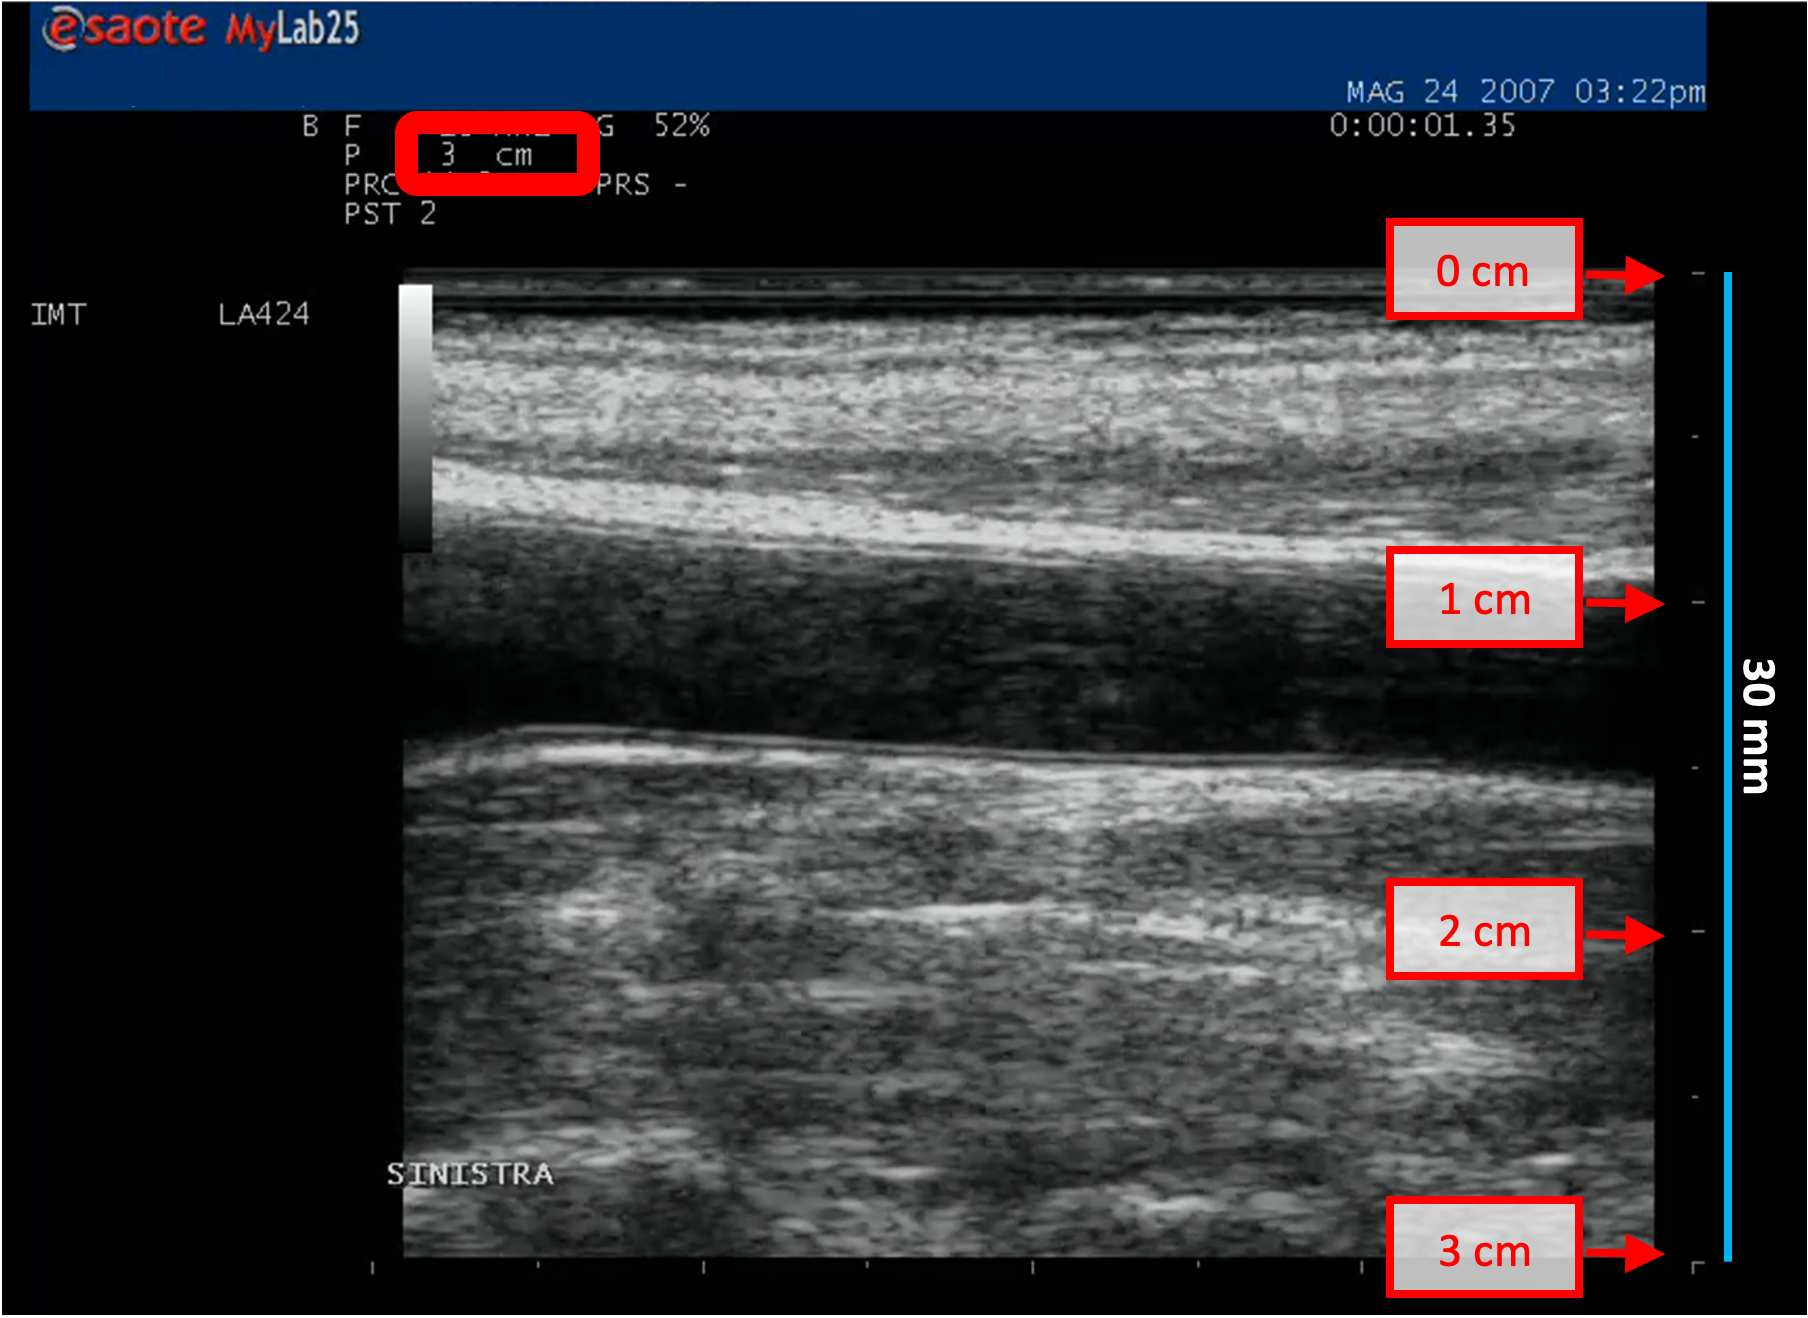

B-mode calibration examples

The following images show examples of calibrations of the b-mode image. Graphic items in red shows where you can find the information about the depth of the image in the ultrasound image.